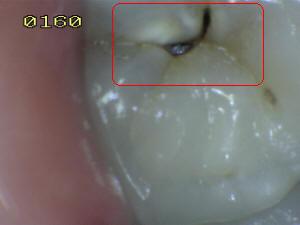

Sistema Internacional para la Detección y Evaluación de Caries (ICDAS)

¿Determine los códigos pertinentes a cada imagen?

Click en el hipervínculo: Para comparar el resultado de su diagnóstico